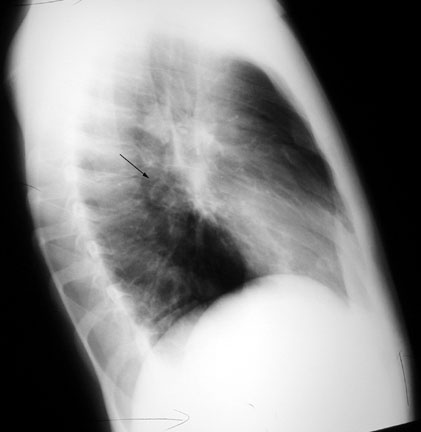

Case 4

Lateral

Labeled Image

What are the contents of a cavity?